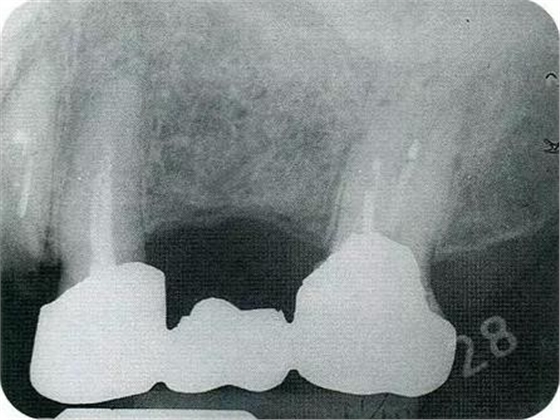

▼圖18-2

圖18-2 拔除近中根的牙齒遠(yuǎn)中面。

▼圖18-3

圖18-3 在其他醫(yī)院進(jìn)行了的修復(fù)處理。拔除了第一磨牙遠(yuǎn)中根的病例。近中根遠(yuǎn)中面殘留著一部分的邊緣。在這種部位很容易滯留牙垢,菌斑的控制會(huì)也很困難。